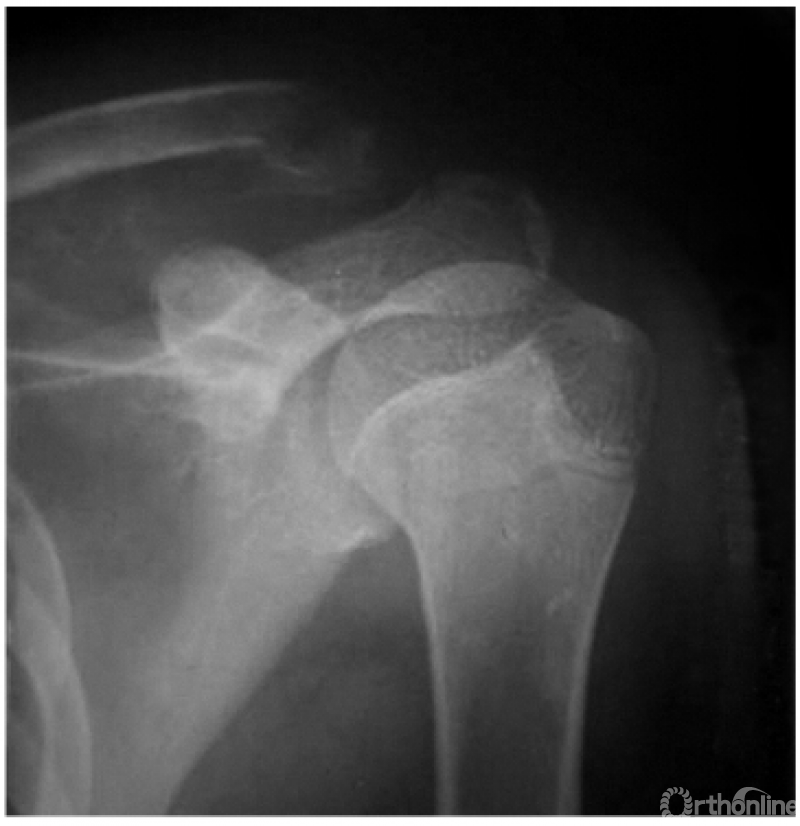

1. 锁骨中段骨折

本例骨折近端因受胸锁乳突肌的牵拉而向后上方翘起,远折端由于喙锁韧带正常而稳定(图1)。